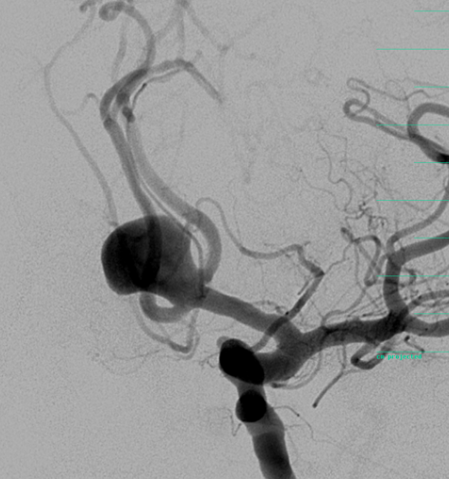

Die Neuroradiologie beschäftigt sich mit der Diagnostik und Therapie von Erkrankungen des Gehirns, des Rückenmarks und der dazugehörigen Gefäße. Wir bieten sämtliche diagnostische und endovaskuläre Verfahren an. Ein besonderer Schwerpunkt liegt auf der interventionellen Behandlung von Gefäßerkrankungen, wie beispielsweise Aneurysmen, Angiomen, duralen AV-Fisteln, angeborenen Gefäßmissbildungen, Engstellen der hirnversorgenden Schlagadern oder der mechanischen Wiedereröffnung von Gefäßen beim akuten Schlaganfall.